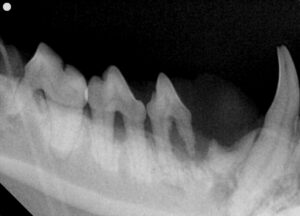

歯科レントゲン検査:歯を支える顎の骨(歯槽骨)が溶けている状態

すると身体は細菌から逃れるために様々な酵素を出して自らの顎の骨を溶かしてしまいます。この状態は歯周炎と呼ばれ歯を支える歯周組織が失われた状態です。結果的に歯がぐらついたり炎症による痛みがでることで猫ちゃんたちの食欲が落ちたり痩せてしまうこともあります。

重度の歯周病を起こしていると診断し、麻酔をかけたうえでのより詳細な検査と治療を提案しました。